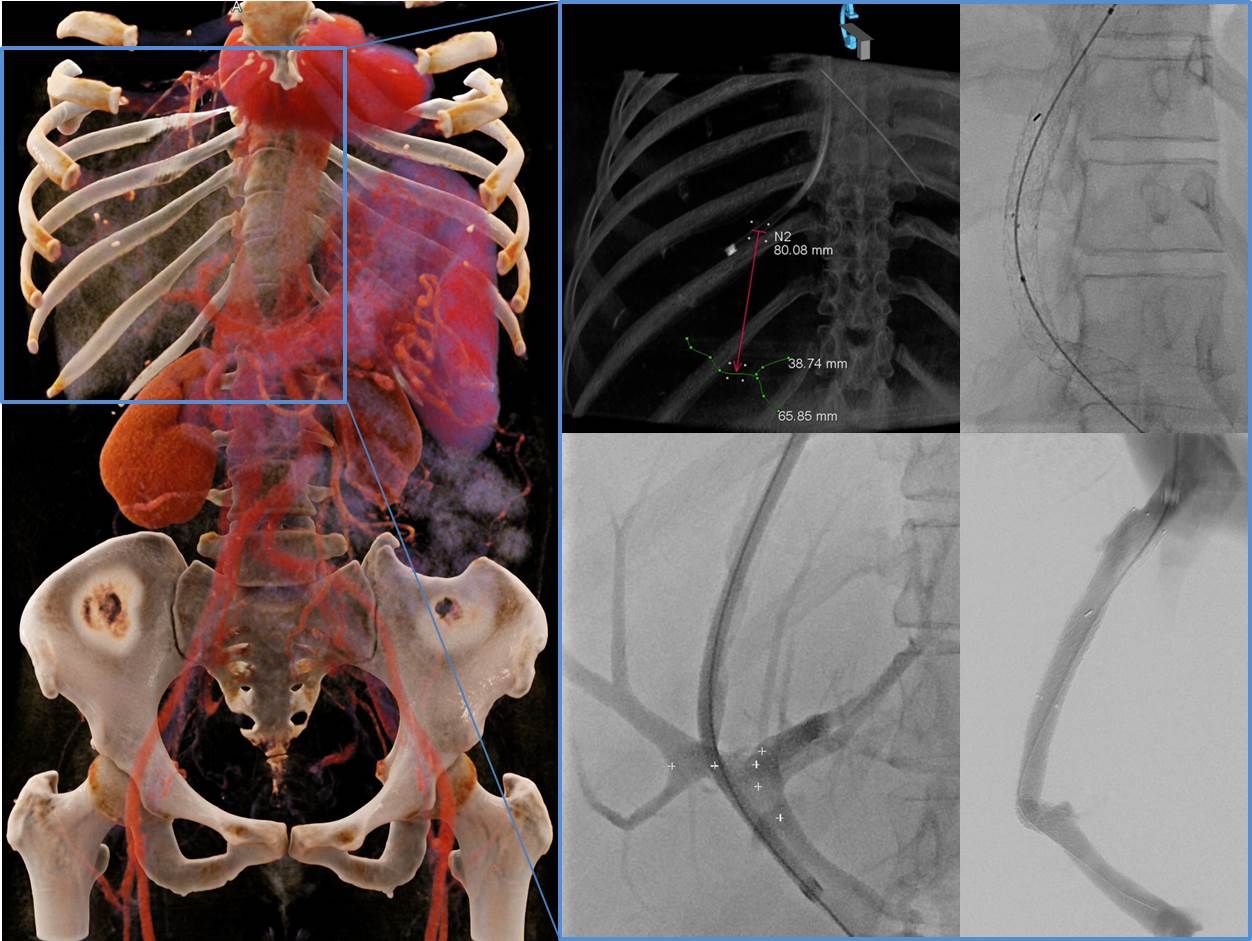

Unser Zentrum zeichnet sich weiterhin durch eine dreidimensionale bzw. räumliche periprozedurale Planung der TIPSS Anlage aus, welche ein insgesamt schonenderes Vorgehen mit verbesserten Ergebnissen ermöglicht.

Planung und Durchführung einer TIPSS Anlage.